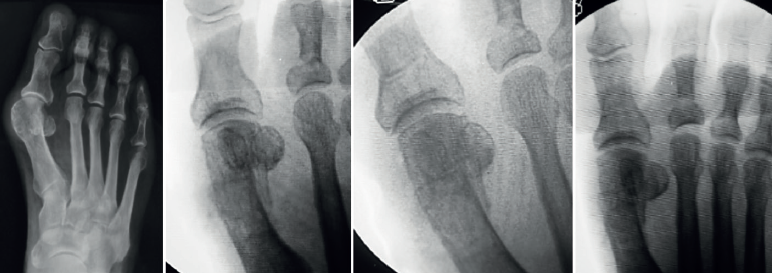

Como vemos, la sugerencia de algún tipo de estabilización debido al riesgo de desplazamiento de la cabeza metatarsiana, menor dolor y edema es una constante en las mencionadas publicaciones. Este concepto es discutible debido a que la osteotomía de tipo Chevron realizada con la rama plantar larga y paralela al piso es intrínsecamente estable y compatible con un postoperatorio de carga precoz (Figuras 4A, B y C) al igual que las osteotomías “con fijación”(17). Los problemas relacionados con el uso de osteosíntesis en las osteotomías metatarsianas ascienden al 10-15% en diferentes series(3,9,11).